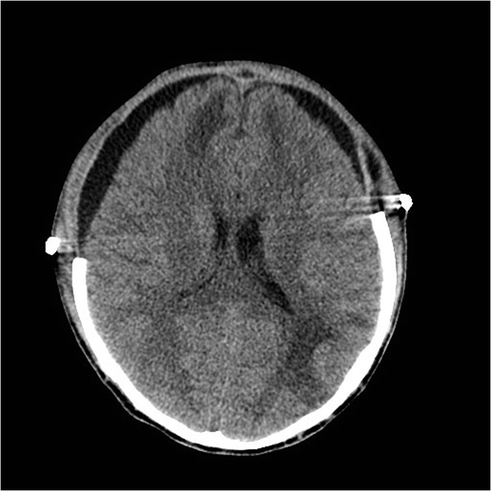

Fig. 19.1

Axial noncontrast head CT demonstrating a left parieto-occipital contrecoup contusion with surrounding hypodensity and subtle bifrontal hypodensities with 5 mm of left to right midline shift. There is a right frontal EVD in place

A 21-year-old male was involved in a T-bone collision while riding a motorcycle wearing a full face helmet. He was a GCS 3T on arrival to the hospital. His head injuries involved a left parieto-occipital contrecoup contusion and subtle bifrontal hypodensities and multiple orthopedic injuries. An EVD was placed and his intracranial pressures were managed medically for the first 5 days. Eventually the right parieto-occipital contusion and bifrontal hypodensities evolved causing 5 mm of left to right midline shift and medically refractory elevated ICPs > 20 mmHg. A wide bifrontal craniectomy was performed. He developed bilateral subdural hygromas 2 weeks after surgery that resolved spontaneously after 3 days of observation. He underwent a bifrontal cranioplasty 4 months after the craniectomy. He was discharged to neuro-rehab with a GCS 14. He has moderate cognitive changes and emotional lability consistent with his frontal lobe injury.